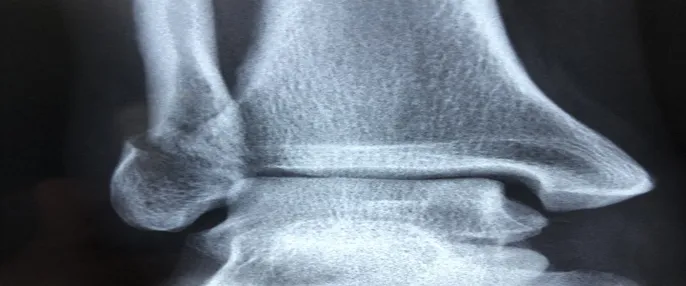

갈비뼈 골절을 진단하기 위해 가장 일반적으로 사용되는 방법은 X-ray 촬영입니다. X-ray는 뼈의 상태를 확인할 수 있는 유용한 도구로서, 갈비뼈의 골절 유무를 파악하는데 중요한 역할을 합니다. 경우에 따라 CT 또는 MRI 같은 추가 검사가 필요할 수 있습니다.